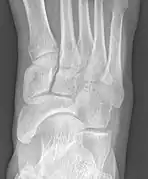

Images radiologiques

De gauche à droite : types 1, 2 et 3

Type 2